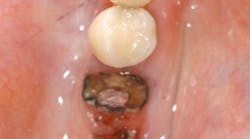

If one is taking certain osteoporosis medications and needs any kind of oral surgery, serious problems could occur. We were made aware of bisphosphonate-related osteonecrosis of the jaw (BRONJ), however, bisphosphonates are not the only culprits. An increasing number of osteonecrosis cases involving the maxilla and mandible have been associated with other antiresorptive (e.g., denosumab) and antiangiogenic therapies. (2) Therefore, the American Association of Oral and Maxillofacial Surgeons (AAOMS) feels it is more appropriate to label this condition medication-related osteonecrosis of the jaw (MRONJ). In 2013, a special committee met to evaluate the current literature and revise the 2009 guidelines to reflect current knowledge in this field. The update contains revisions to diagnosis, staging, and management strategies, and highlights current research status. (2)

MRONJ adversely affects the quality of life, causing significant morbidity. Protocols for management of patients with MRONJ, or those at risk for it, were presented in the AAOMS updated Position Paper on Bisphosphonate-Related Osteonecrosis of the Jaw in 2009. (3) The new Position Paper is extremely detailed, and includes background material, risk factors for MRONJ, management strategies for patients treated with antiresorptives or antiangiogenics, treatment goals, and much more. (2)